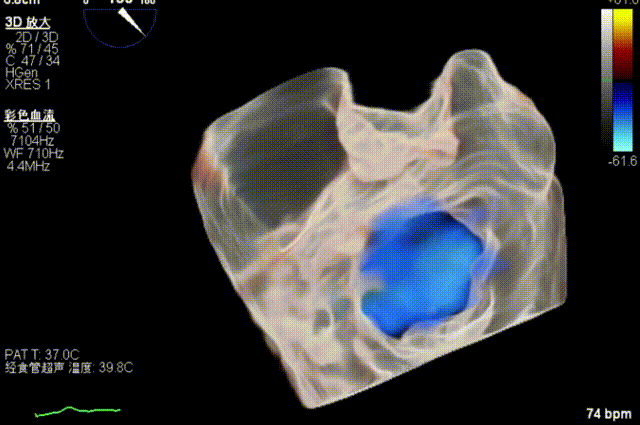

患者为原发性二尖瓣反流(DMR),收缩期可见二尖瓣反流信号,反流位于 2 偏 3 区,基线期二尖瓣反流程度4+。

前叶长度 15.7mm,后叶长度 12.7mm,后叶脱垂宽度13.9mm,脱垂高度4.76mm, 瓣环直径37.1mm,VC:4*7mm, MVA约4cm² 。瓣叶质地较差,腱索断裂、后瓣叶脱垂。

术前超声